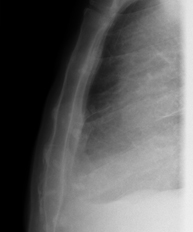

- Tòrax

- RX Tòrax

Tècnica que usa els raigs X a través de la qual s'obtenen imatges de la caixa toràcica (cor, pulmó, arcs costal, clavícules, etc.) per al seu estudi. - RX Ester